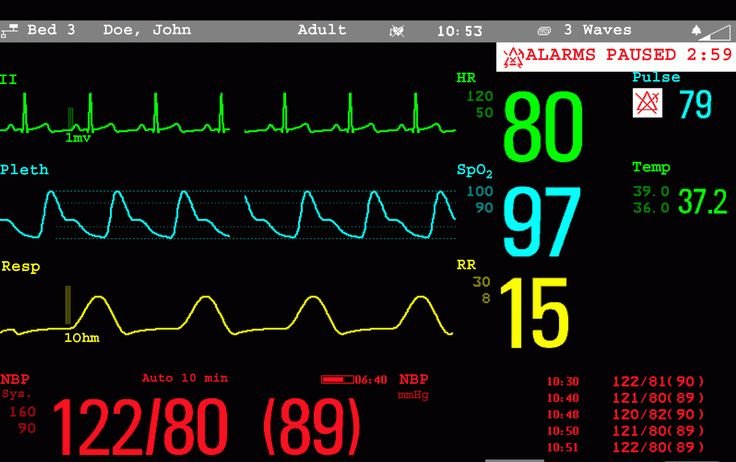

Myocardial Perfusion Imaging (MPI) is a non-invasive procedure utilized to assess significant coronary artery disease (CAD). This diagnostic and prognostic examination determines the extent and location of impaired blood flow to the heart, as well as evaluates pumping function and the presence of scarred heart tissue. A small amount of radiotracer is injected intravenously during both resting and stress states, achieved through physical exertion (such as treadmill exercise) or pharmacological stress. Throughout the procedure, blood pressure and electrocardiogram monitoring are conducted. Healthy heart muscle, receiving adequate blood flow, will accumulate more of the radiotracer compared to regions supplied by diseased coronary arteries.

Resting ECG

Stress ECG